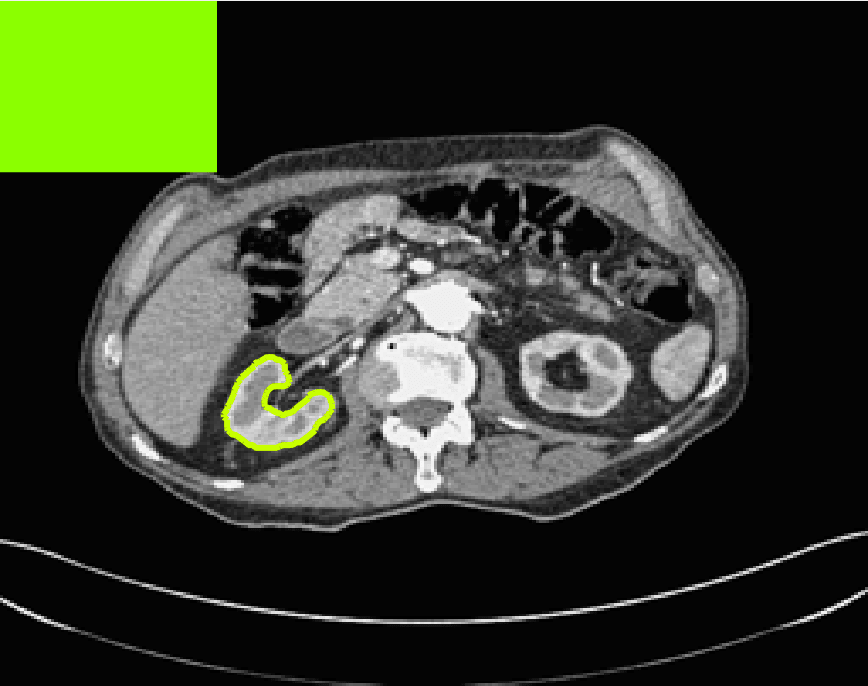

Test Images. We will perform initial tests on the images shown in Figs. 5–7. We have provided the ground truth and initialisation used for each image. Test Images 1–3 are synthetic, Test Image 4 is an MRI scan of a knee, Test Images 5–6 are abdominal CT scans, and Test Images 7–9 are lung CT scans. They have been selected to present challenges relevant to the discussion in §2. We focus on medical images as this is the application of most interest to our work. In the following we will discuss the results in terms of synthetic images (1–3) and real images (4–9). We also test the proposed approach on a larger data set of 30 CT images (a sample of which is presented in Fig. 18), comparing against existing selective methods detailed in §3.

In order to further establish the robustness of our method, we now introduce the results of testing our approach against competing interactive segmentation methods on a larger data set. The results are presented in Fig. 17, showing a boxplot of accuracy in terms of TC on a set of 30 CT images (excluding outliers). The target structure we consider is the spleen, as this consists of a relatively homogeneous foreground, appropriate for the approach considered. The data has been manually contoured providing ground truth data for the image set. We compare CAC Nguyen:12 and SRW SRW against our method with five variations of user input for each image. It is worth emphasising here that the input used in the tests is identical for each approach and was not refined in any way. It was designed to mimic what a user, unfamiliar with each approach, might select intuitively. A representative example for three images is shown in Fig. 18. This shows foreground (red) and background (blue) user input regions. For our method, we define the red region as as discussed in §1 and enforce hard constraints on the blue region. We refer to the results of the proposed approach using this input as Ours (i). We also include results of randomising the user input in an identical way to §7.3. For each image we generate 1000 simulated user input choices, which we present as Ours (ii). It is important to note that the difference between Ours (i) and (ii) is only the definition of . The method and parameters are fixed between each.